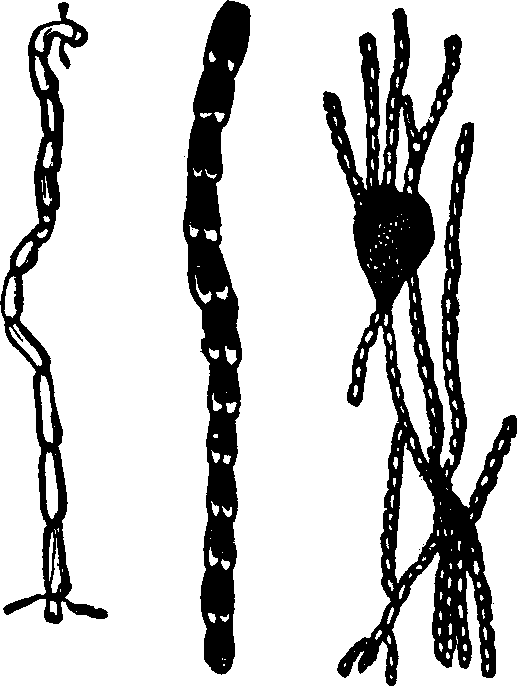

Generation. So long as the vital principle remains in the sperm-cell, it lies dormant. That part of the cell which contains this principle is called the spermatozoön, which consists of a flattened body, having a long appendage tapering to the finest point. If it be remembered that a line is the one-twelfth part of an inch in length, some idea may be formed of the extreme minuteness of the body of a human spermatozoön, when we state that it is from 1/800 to 1/600 part of a line, and the filiform tail 1/50 of a line, in length. This life-atom, which can be discerned only with a powerful magnifying glass, is perfectly transparent, and moves about by executing a vibratile motion with its long appendage. Within this speck of matter are hidden the multifarious forces which, under certain favorable conditions, result in organization. Magnify this infinitesimal atom a thousand times, and no congeries of formative powers is perceived wherewith to work out the wonders of its existence. Yet it contains the principle, which is the contribution on the part of the male toward the generation of a new being.

Fig. 1. A. Human

Spermatozoön magnified about 3,800 diameters. B. Vertical and

lateral views of spermatozoa of man. C, D, E, F. Development of

spermatozoa within the vesicles of evolution. G. Cell of the sponge

resembling a spermatozoön. H. Vesicles of evolution from the

seminal fluid of the dog in the parent cell I. Single vesicles of

different sizes. J. Human spermatozoön forming in its cell.

K. Rupture of the cell and escape of the spermatozoön.

[pg 16]In several insect families, the species is not wholly represented in the adult individuals of both sexes, or in their development, but, to complete this series, supplementary individuals, as it were, of one or of several preceding generations, are required. The son may not resemble the father, but the grandfather, and in some instances, the likeness re-appears only in latter generations. Agassiz states: "Alternate generation was first observed among the Salpæ. These are marine mollusks, without shells, belonging to the family Tunicata. They are distinguished by the curious peculiarity of being united together in considerable numbers so as to form long chains, which float in the sea, the mouth(m) however being free in each.

"Fig. 2. The individuals thus joined in floating colonies produce eggs; but in each animal there is generally but one egg formed, which is developed in the body of the parent, and from which is hatched a little mollusk.

"Fig. 3, which remains solitary, and differs in many respects from the parent. This little animal, on the other hand, does not produce eggs, but propagates, by a kind of budding, which gives rise to chains already seen in the body of their parent(a), and these again bring forth solitary individuals, etc."